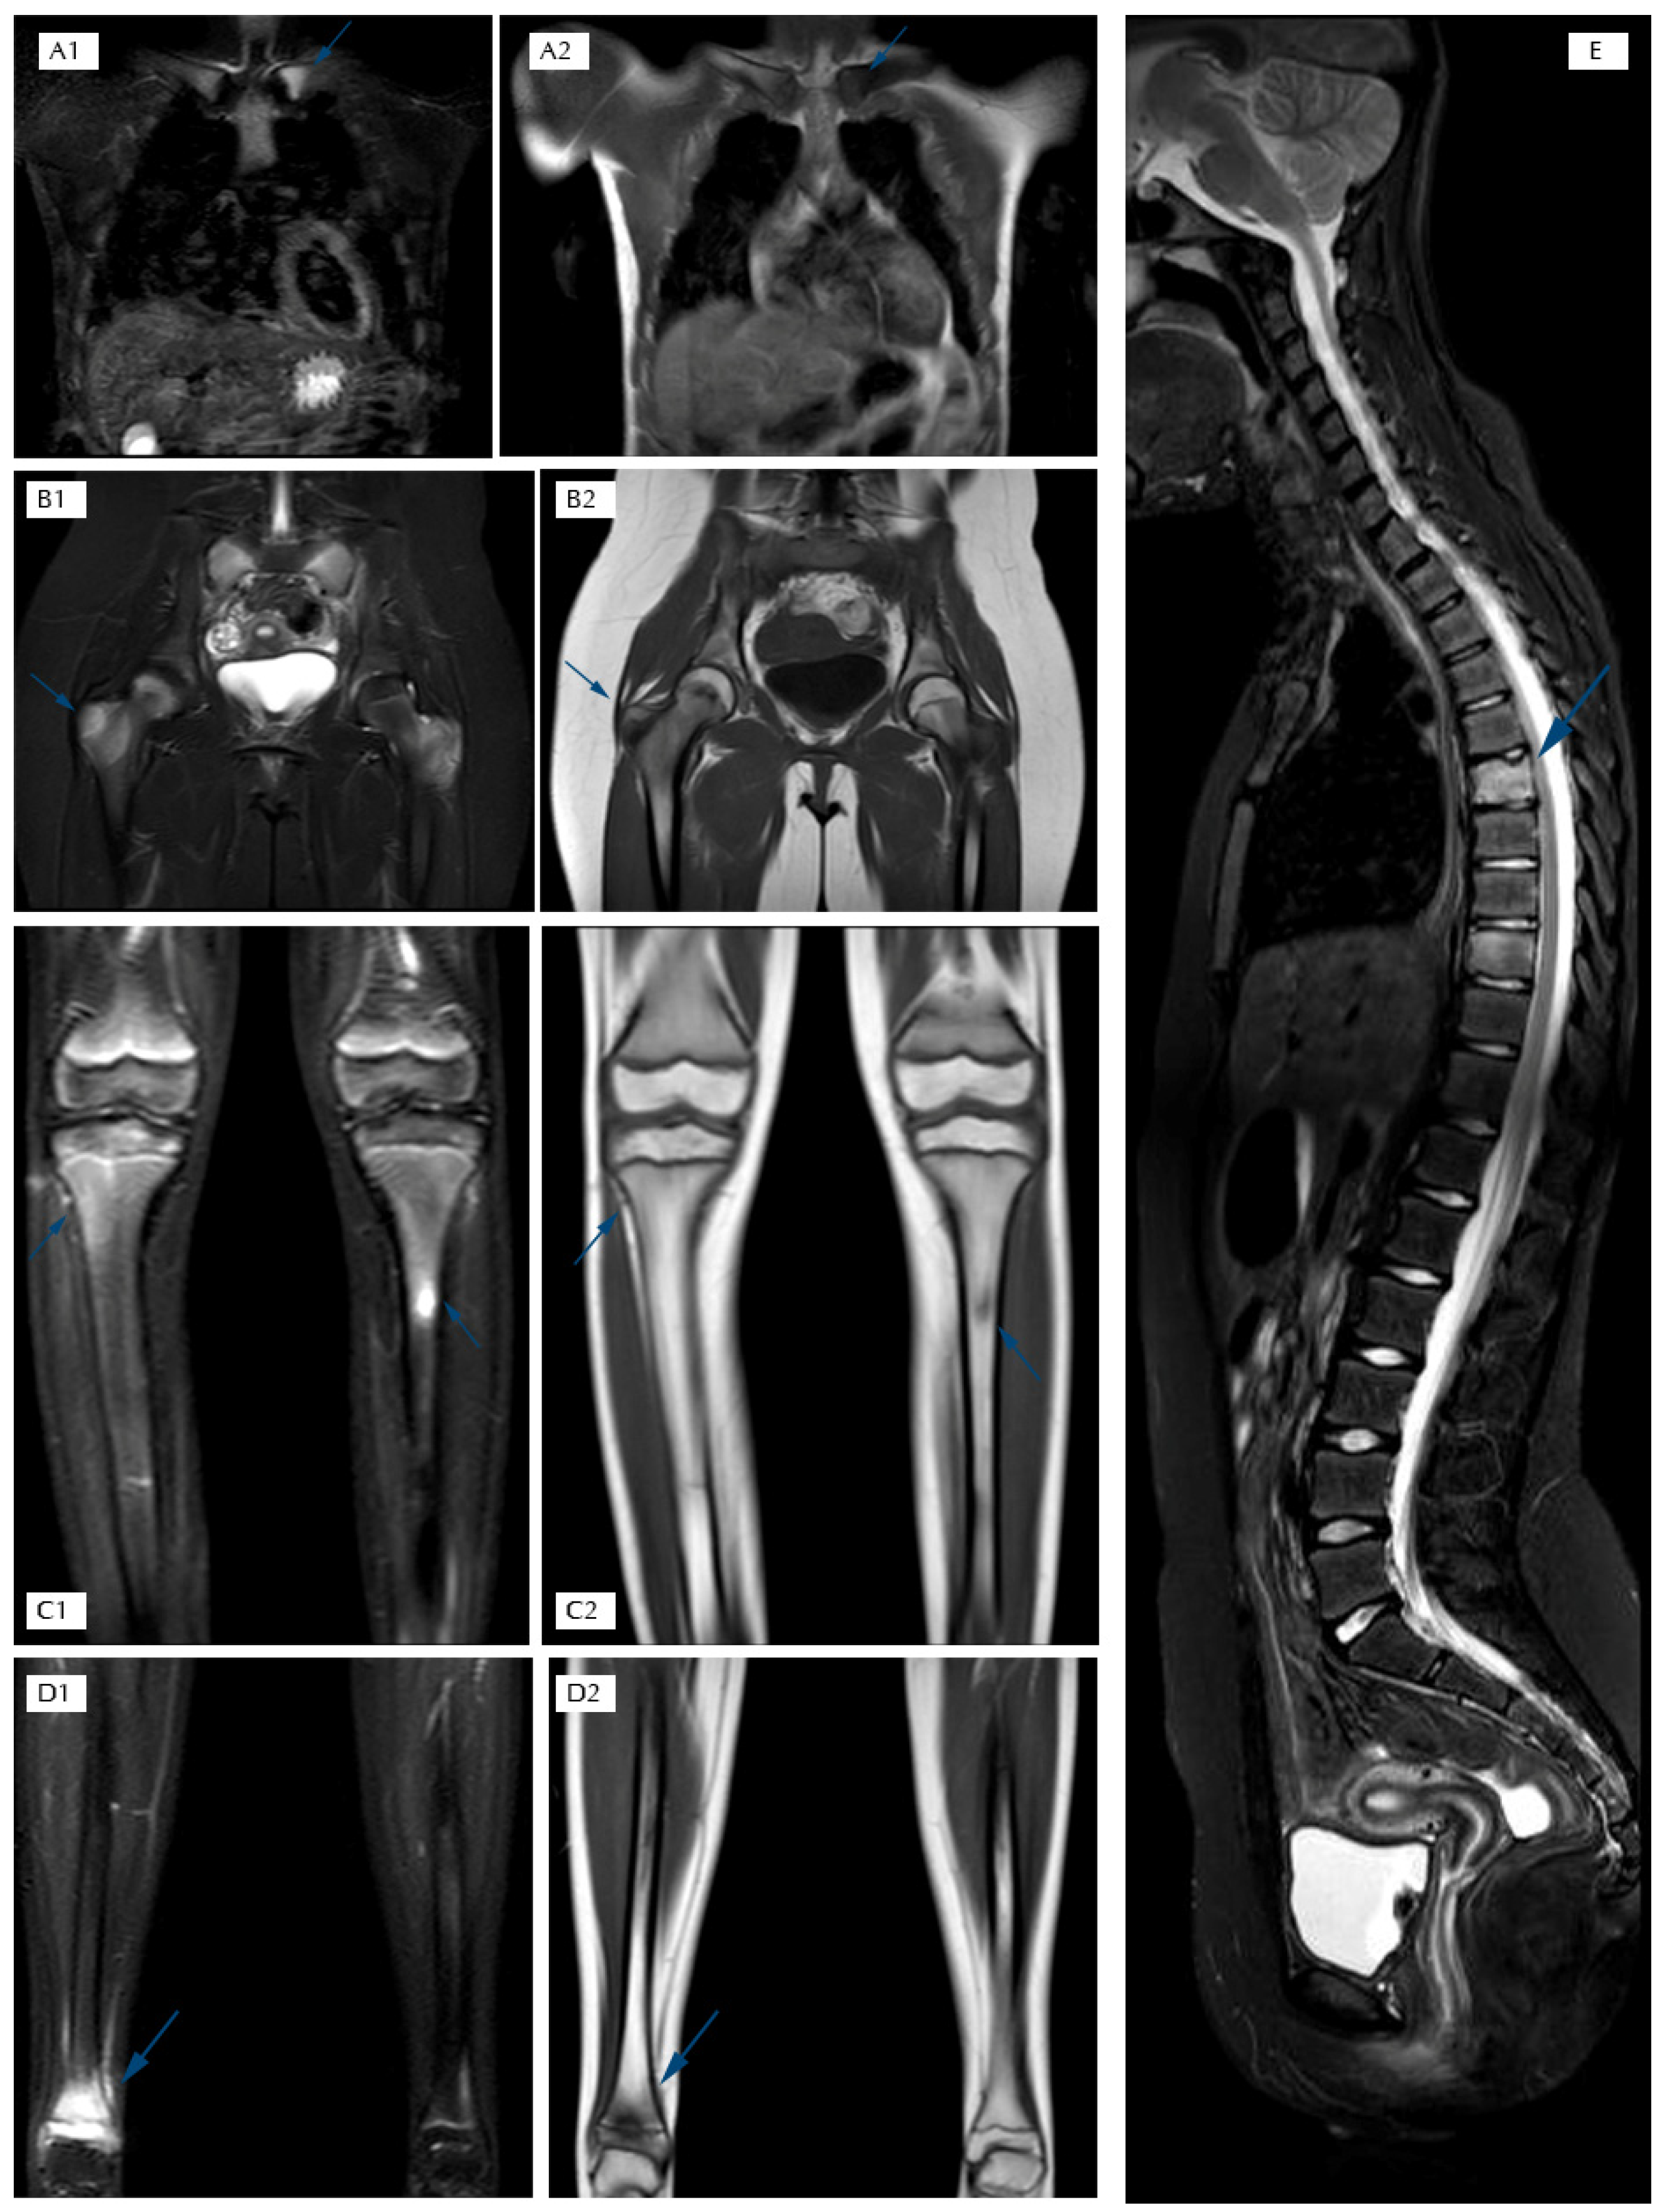

- Magnetic Resonance Imaging (MRI) represents the most important diagnostic test to study inflammatory bone pathology in the initial phases of the disease, because of its high sensitivity for bone marrow edema even before the appearance of osteolysis and/or osteosclerosis [29,30,31]. Furthermore, this method does not involve exposure to ionizing radiation, and it has replaced bone scintigraphy in the diagnostic framework phase [29,30,31,32]. In CNO management, WB-MRI is usually performed and, thanks to its capability of monitoring the response to treatment, this represents the gold standard imaging test for diagnosis and follow-up. Through WB-MRI, it is also possible to visualize “silent lesions”, study the synovium, characterize the disease as unifocal or multifocal, recognize axial skeletal involvement, and identify the best site for performing bone biopsy [33]. Inflammatory lesions of CNO typically appear as hyperintense on T2-weighted sequences such as STIR (Short Tau Inversion Recovery) or TIRM (Turbo Inversion Recovery Magnitude) and hypointense on T1-weighted sequences (Figure 2) [34]. Acute lesions may also demonstrate restriction of the diffusion (DWI and ADC map sequences).

Figure 2. T2 STIR and T1 TSE sequences in the coronal plane: (A1–D2) STIR sequence in the sagittal plane of the spine; (E) STIR hyperintensity and T1 hypointensity are suggestive of bone marrow edema; (A1,A2) edema of the left clavicle in T2 STIR and T1 hypointensity; (B1,B2) edema of the greater trochanters in T2 STIR and T1 hypointensity; (C1,C2) edema of the proximal metaphysis and diaphysis of tibias in T2 STIR and T1 hypointensity; (D1,D2) edema of the distal metaphysis and epiphysis of the right tibia in T2 STIR and T1 hypointensity; (E) edema of two dorsal vertebral bodies in T2 STIR.